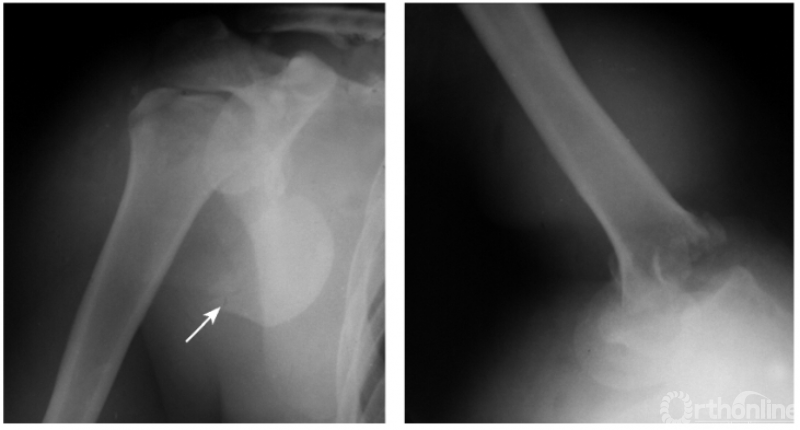

肩关节后脱位是所有大关节脱位中最易误诊的一种损伤,其误诊率可高达60%,因此该病有“诊断的陷阱”之称,有学者指出肱骨头关节面与盂前缘距离大于6mm时应高度怀疑有后脱位的可能。

此外,由于脱位后上臂外旋受限,因此即使在最大外旋位拍片时仍不能显示出肱骨颈及大结节的轮廓。例:肱骨头离开关节盂而向后外上方(肩峰之下)移位且内旋,致肱骨头与肱骨干在一直线上,招致肩肱曲线不流畅,肱骨头关节面与盂前缘距离大于6mm并小结节骨折(如下图)。